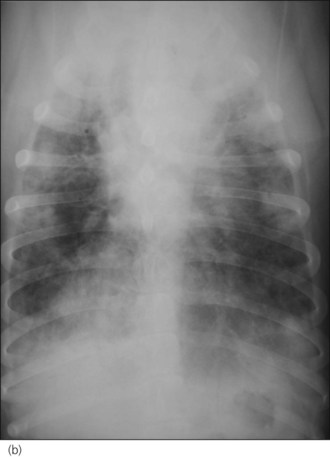

An intravenous catheter was placed in a cephalic vein and blood obtained via the catheter for an emergency database to be performed. This revealed severe anaemia (manual packed cell volume (PCV) 14%, reference range 37–55%) with raised plasma total solids (78 g/l, reference range 49–71 g/l); however, the serum was icteric in appearance. These findings were consistent with the suspicion of haemolytic anaemia. An in-saline agglutination test was performed (Box 33.3) and found to be strongly positive (Figure 33.1). Peripheral blood smear examination revealed a strongly regenerative anaemia with marked polychromasia and anisocytosis and an increase in nucleated red blood cells; marked spherocytosis was also identified. Platelet numbers were adequate, and a moderate subjective left-shifted neutrophilia and a monocytosis were suspected (see Ch. 3).

BOX 33.3 In-saline agglutination test for autoagglutination

One or more drops of fresh blood (or blood from an EDTA tube) are placed on a glass slide and an equal volume of normal saline added. The slide is gently rotated and then examined for evidence of macroscopic agglutination after approximately 1 minute. The slide is then examined microscopically as well (Figure 33.1). Saline is added to differentiate true agglutination from rouleaux formation. Rouleaux are chains of red blood cells stacked like coins, and are especially common in cats and animals with inflammation. They should be dissipated by the addition of saline.

Figure 33.1 Microscopic in-saline agglutination (a) ×100 and (b) ×200 magnification.

(Photographs courtesy of Kate English)

In addition to documenting haemolytic anaemia, definitive diagnosis of IMHA requires marked spherocytosis, spontaneous autoagglutination or a positive direct Coombs’ test to be identified. In the author’s experience, most dogs presenting as emergencies with clinically significant IMHA have autoagglutination and/or marked spherocytosis at the time of presentation. The diagnosis can usually therefore be made on an emergency basis without the delay involved in awaiting the results of a Coombs’ test.